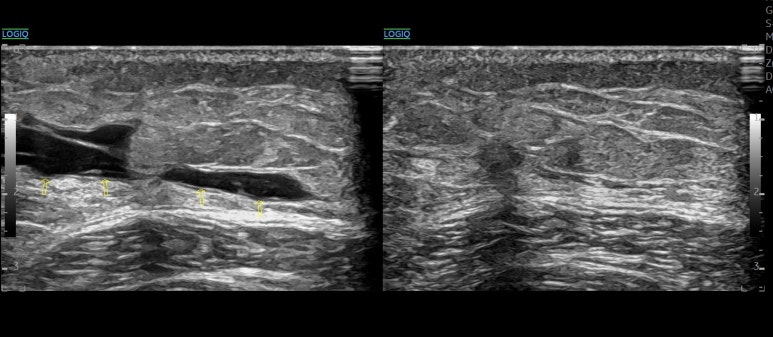

초음파상 피가 굳어 보이는 고에코 상태나 복잡한 격막이 관찰되더라도, 80% 이상의 사례에서 성공적으로 배액이 가능했던거죠. 배액술을 받은 모든 환자가 즉각적인 증상 호전을 보이기도 했고요. * * * ## 2가지 논문을 종합해본 결과즉, 6개월까지는 몸이 스스로 해결하려고 노력하는 기간이자 비침습적으로 해결할 수 있는 ## 이상적인 치료 기간인 셈입니다. * * * ## 5. 한의 초음파의 핵심경혈 주변을 정밀하게 타겟팅! 한의학에서는 이런 혈종을 치료할 때 '경혈' 주변의 해부학적 구조를 면밀히 살핍니다. 초음파를 통해 주변 근육인 경근(經筋) 조직의 손상이나 혈종의 정확한 깊이를 확인하는 것이죠. [하지부] 허벅지의 복토혈(伏兎) 엉덩이의 환도혈(環跳) 과 같은 주변에 깊숙이 자리 잡은 혈종은 손으로 만져서는 정확한 위치를 알기 어렵습니다.

초음파로 병변 부위에 딱 맞춰 시술해야 주변 조직 손상 없이 어혈을 빠르게 제거할 수 있고요. 치료 직후 혈종이 빠르게 사라집니다.